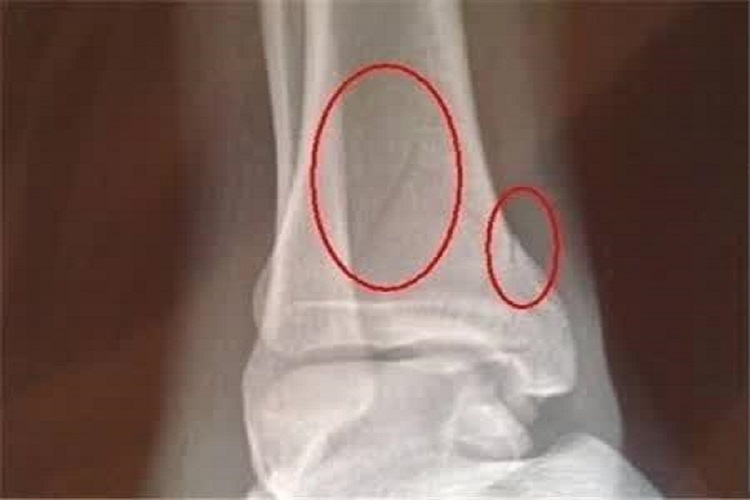

左外踝骨折后能走路和康复的时间因人而异,受到骨折严重程度、治疗方法以及个体差异等多方面因素的影响。

- 如果骨折没有明显的移位,只是骨裂或者骨折断端对位良好,通常在6-8周左右可以开始尝试部分负重行走,经过3-4个月的康复,基本可以恢复正常活动。

- 例如骨折断端明显移位、粉碎性骨折,或者合并有周围韧带的严重损伤,恢复时间会明显延长,可能需要8-12周才能开始部分负重行走,完全康复可能需要6个月甚至更长时间。